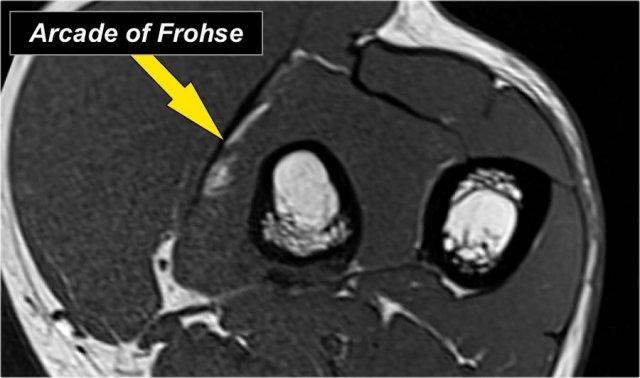

Radial nerve

Dây thần kinh quay có thể được xác định rõ nhất ở mức chỏm xương quay, nơi có thể quan sát thấy các nhánh nông và nhánh sâu trong ống xương quay (mũi tên).

This is a very consistent place to find the radial nerve.

Các nhánh quay sâu tạo thành thần kinh gian cốt sau xuyên qua cơ ngửa tại cung Frohse (mũi tên).